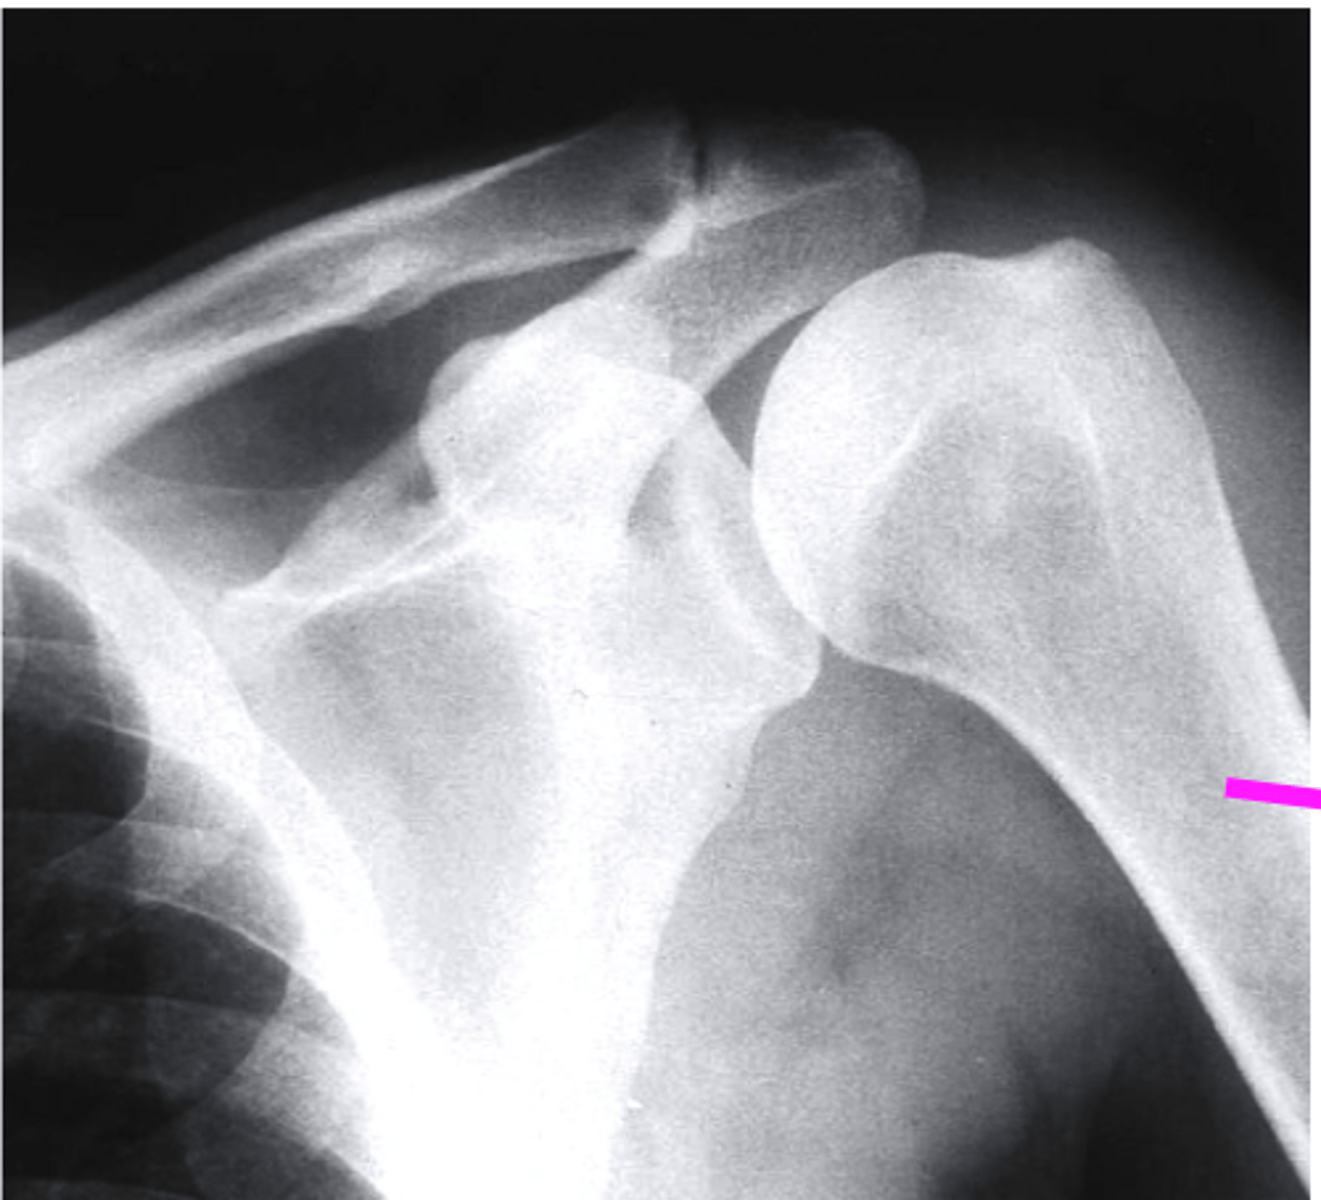

AP + ER

What view is this?

clavicle

what does the pink line point to?

spine of scapula

coracoid process

AC joint

acromion

Humeral Head

Greater Tuberosity

lesser tuberosity

Anatomic Neck of Humerus

Surgical Neck of Humerus

Shaft of Humerus

glenoid fossa

body of scapula

axillary border of scapula

vertebral border of the scapula